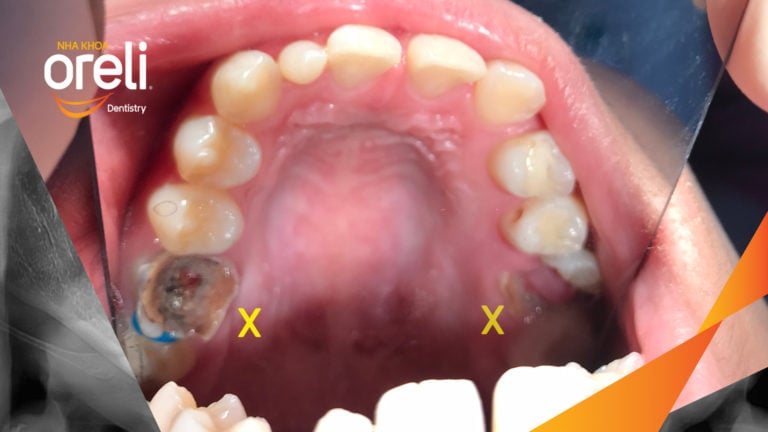

Ca niềng răng đặc biệt: kéo răng 7, 8 thay thế 3 răng 6 bị hư tại Oreli Niềng răngDi gần răng 7 8 Xem thêm